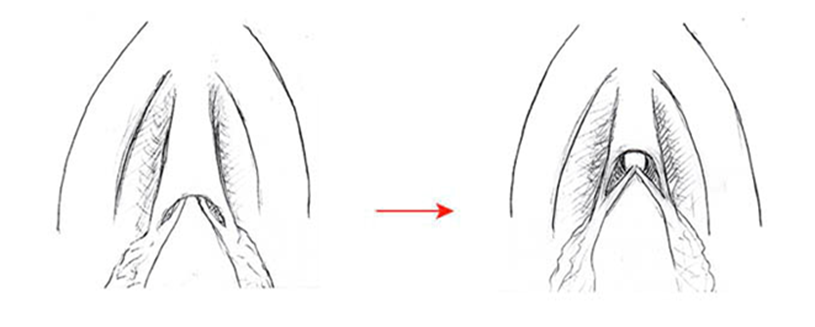

- یک سونوگرافی از اندامهای لگنی.